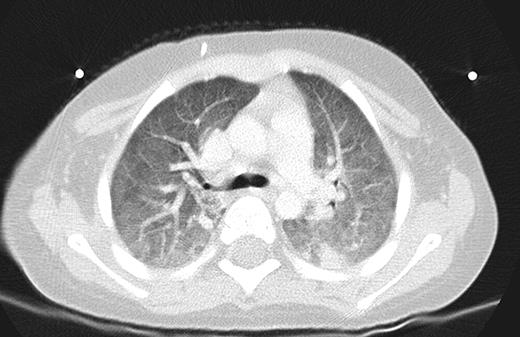

Our Patient, 8 weeks into chemotherapy for newly diagnosed ALL, presented with high grade fevers and poor activity. Patient was admitted 3 weeks prior for Bacillus cereus bacteremia. Additionally the patient had been on broad spectrum antibiotics on 2 occasions for febrile neutropenia episodes within the past 2 weeks. Patient had minimal respiratory symptoms at this presentation and recovered from pancytopenia at the time of this presentation. CT scans and chest x-ray (Figures 1 and 2) showed diffuse marked ground glass opacities with dependent consolidation in the lungs. On day 3 of admission, bronchoalveolar lavage (BAL) was preformed and empiric trimethoprim-sulfamethoxazole was initiated in addition to broad spectrum antibacterial, antifungal and antiviral medications.

Ground Glass Opacities on CT Chest